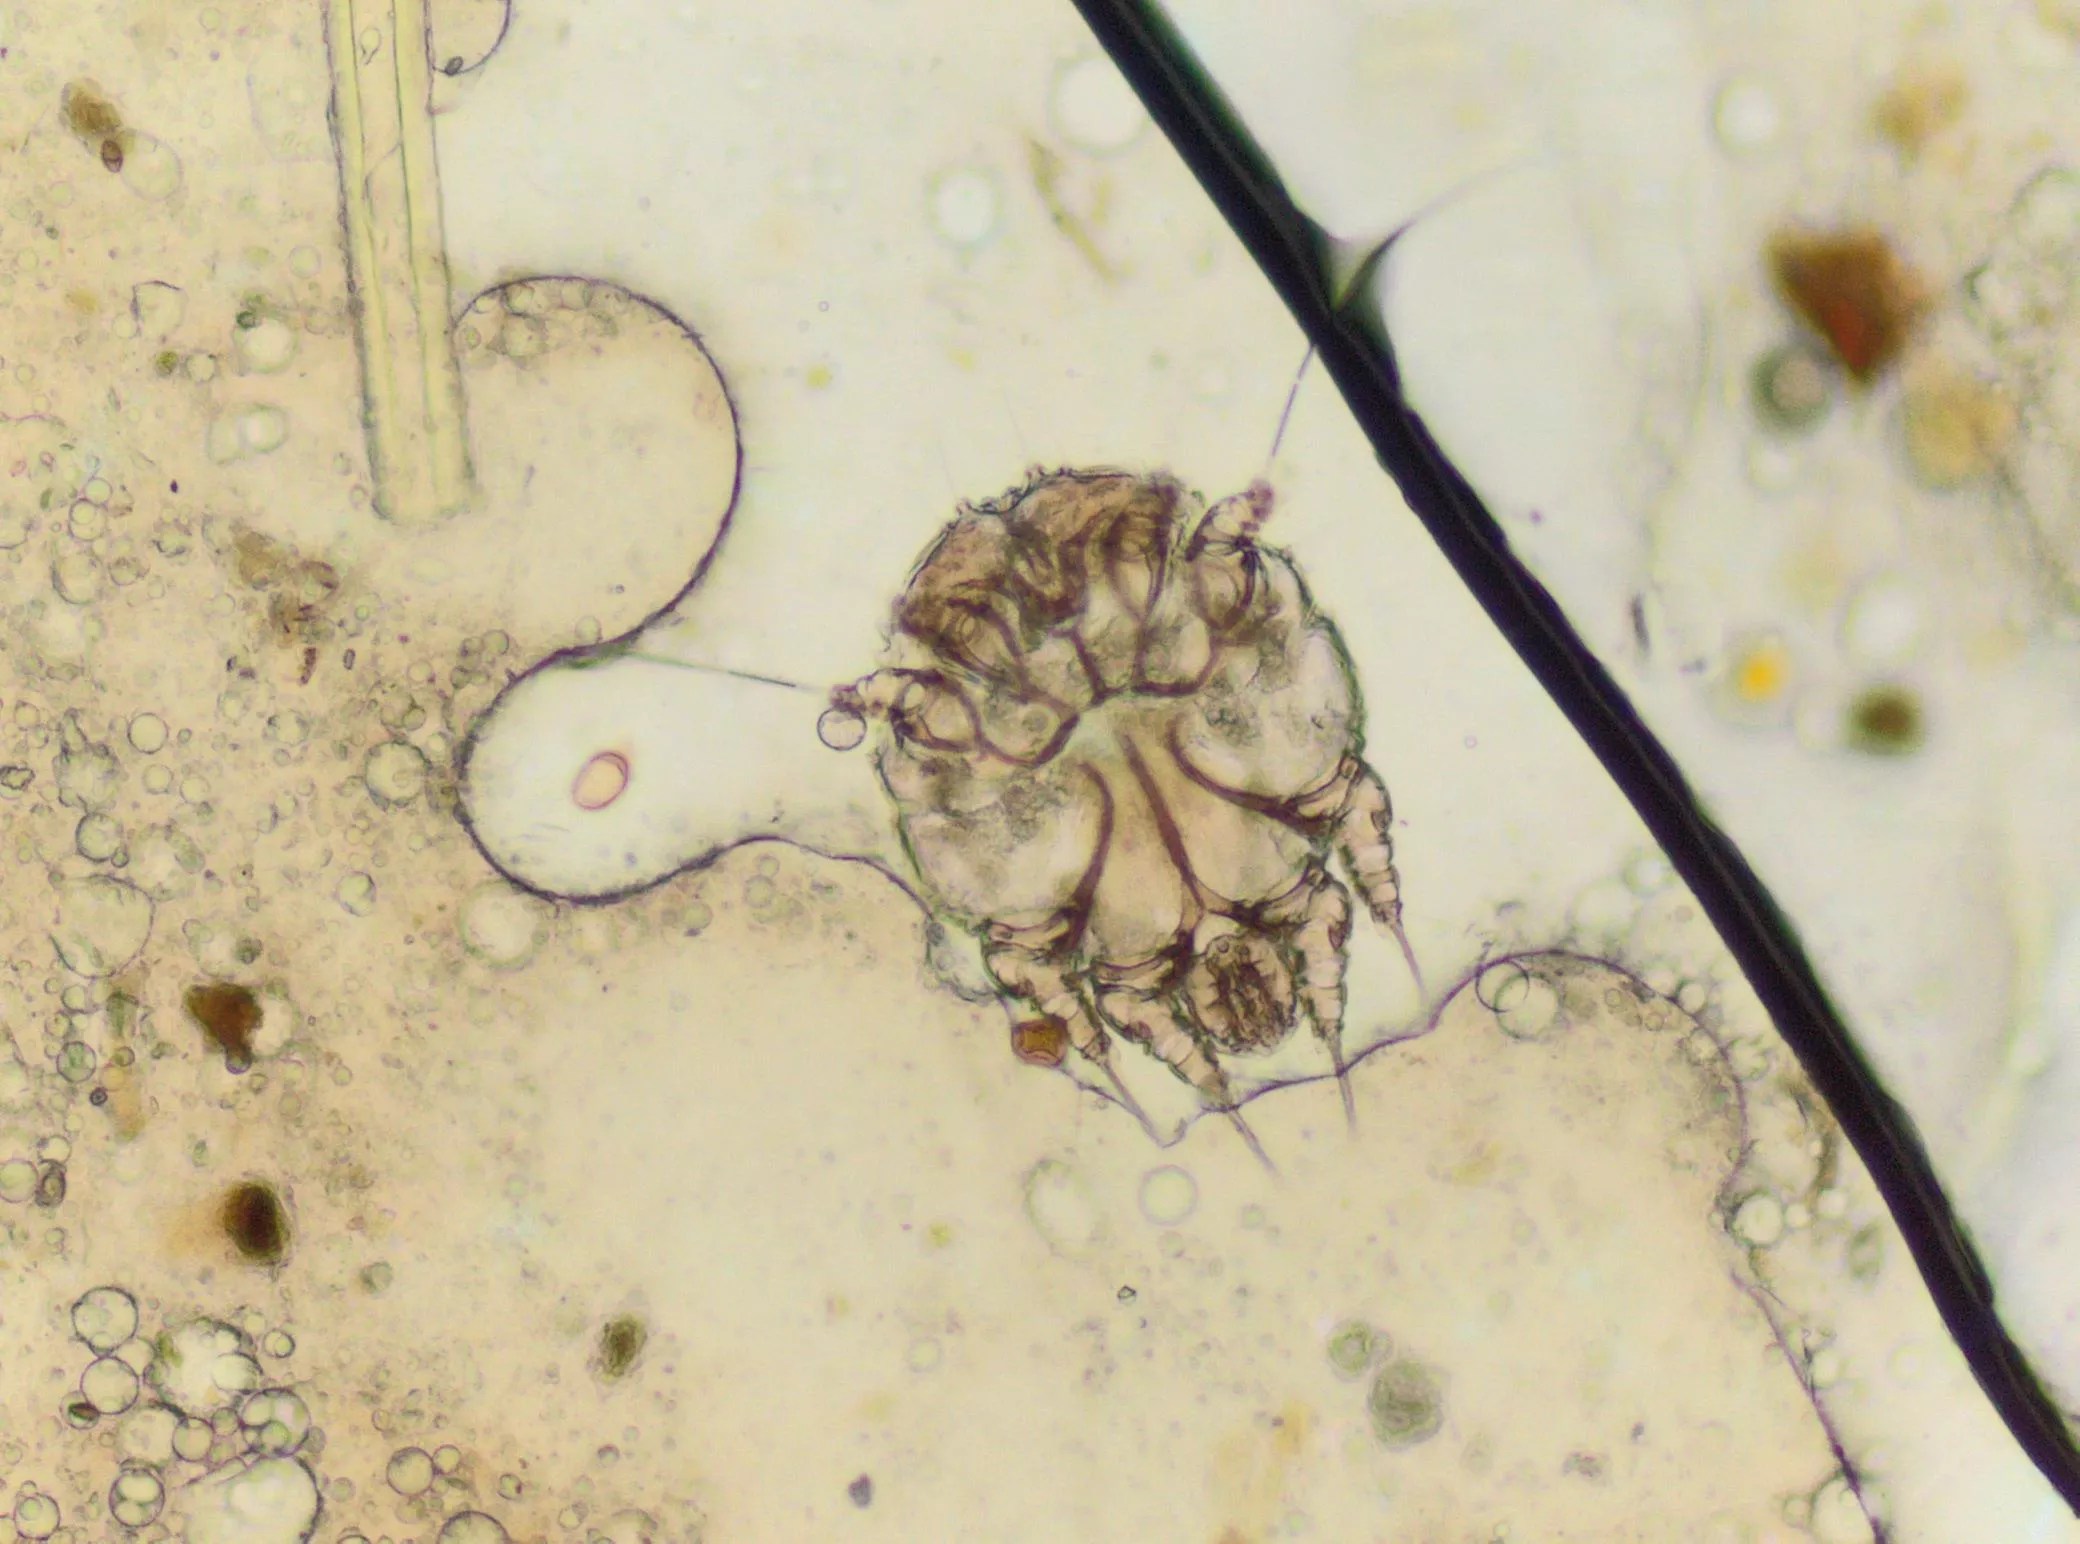

Scabies occurs when a human itch mite burrows into the upper layer of the skin, where it lives and lays its eggs. When a person is infected with scabies for the first time, they can be contagious, even while not displaying symptoms for weeks.

“The most common symptoms of scabies are intense itching and a pimple-like skin rash. The scabies mite usually is spread by direct, prolonged, skin-to-skin contact with a person who has scabies,” according to the Centers for Disease Control and Prevention (CDC). “Prisons are often sites of scabies outbreaks,” the CDC continued.